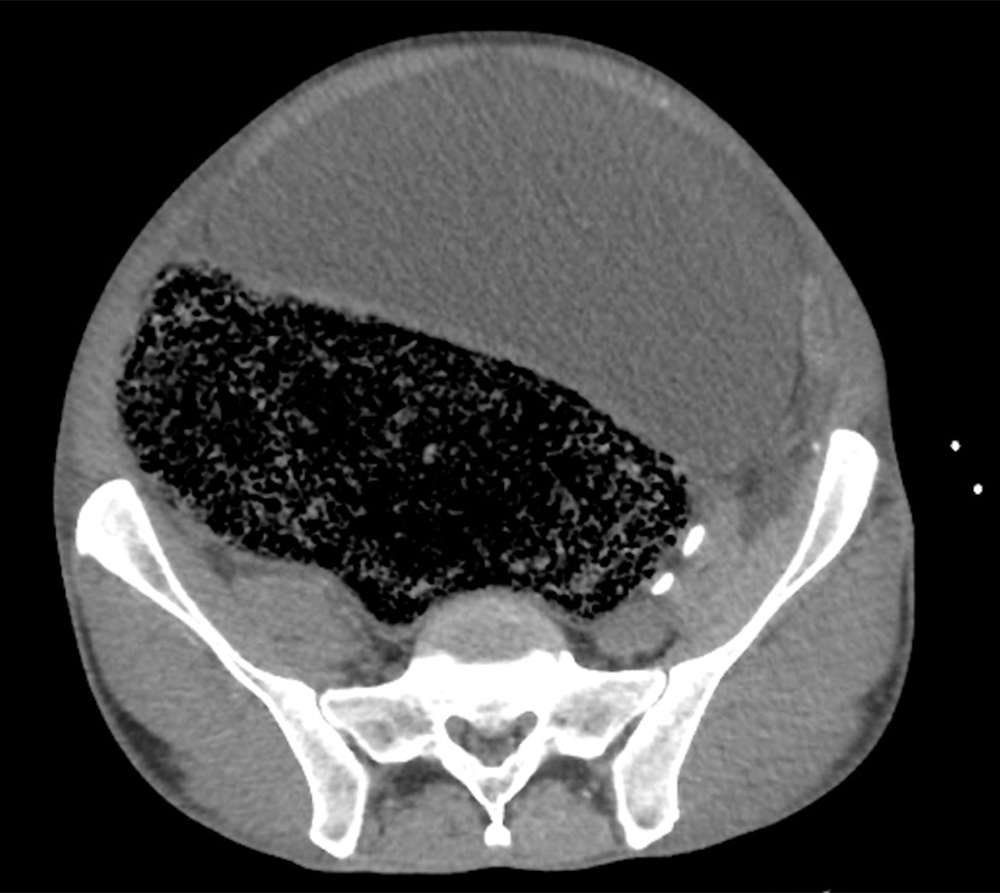

След преглед на ректума лекарите установяват, че мъжът е имал сериозен запек. Скенер на коремната кухина показва, че става дума за потенциално опасен за живота Синдром на коремното отделение (повишено налягане в коремната кухина).

Изпражненията са се струпали до такава степен, че са разширили голямото черво и са оказали силен натиск върху неговата дясна вътрешна срамна артерия. Това налягане е предизвикало болката в крака и съответно е довела до парализата.

Мястото, където фекалиите са оказали натиск върху артерията. Източник: BMJ Case Reports.